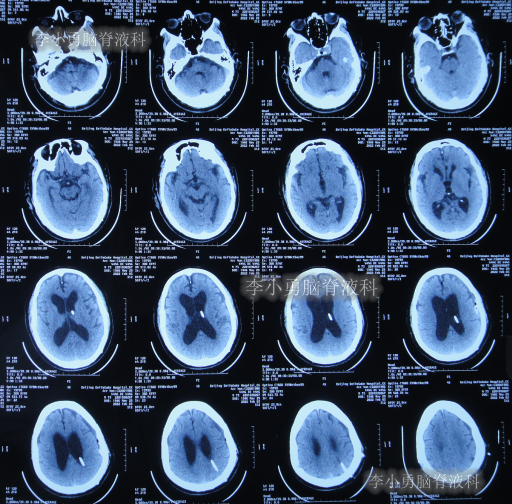

发现脑积水后8天即2020年11月6日,就诊于第2家的上海的某三甲医院,入院后再次检查(图-2)后诊断为正常压力脑积水。

图-2:2020年11月11日头部核磁